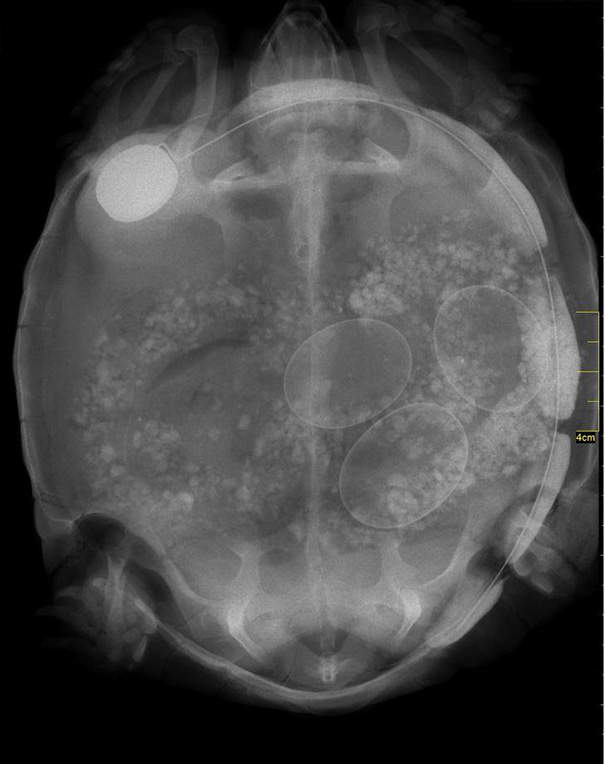

▼烏龜但看起來真的很玄妙...

圖片來自:boredpanda